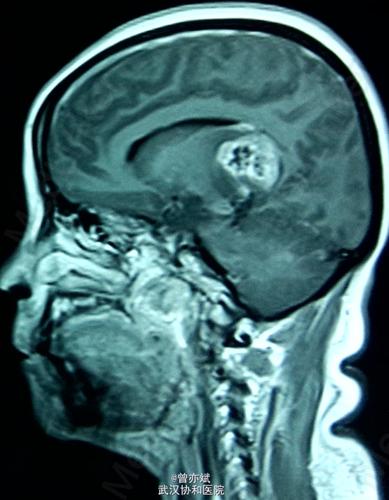

mr:见左侧脑室旁脑梗塞.

朱育霆 2岁 左侧脑室及丘脑占位 13903809976(副本)

侧脑室占位一例